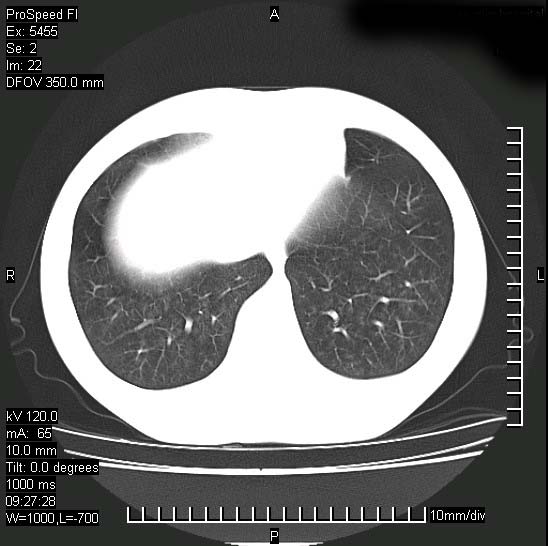

以下是引用zjzjr在2008-12-3 20:50:00的发言:[br]考虑泛细支气管肺炎,建议进一步检查除外肺出血性疾病如含铁血黄素沉着症、肺肾综合征等。

以下是引用zjzjr在2008-12-3 20:50:00的发言:[br]考虑泛细支气管肺炎,建议进一步检查除外肺出血性疾病如含铁血黄素沉着症、肺肾综合征等。

以下是引用光线在2008-12-3 20:19:00的发言:[br]双肺间质性改变。